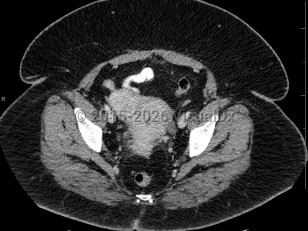

Rectal carcinomaRectal carcinoma

Uterine fibroidsUterine fibroids

Bladder cancerBladder cancer

EndometriosisEndometriosis

Ovarian cancerOvarian cancer